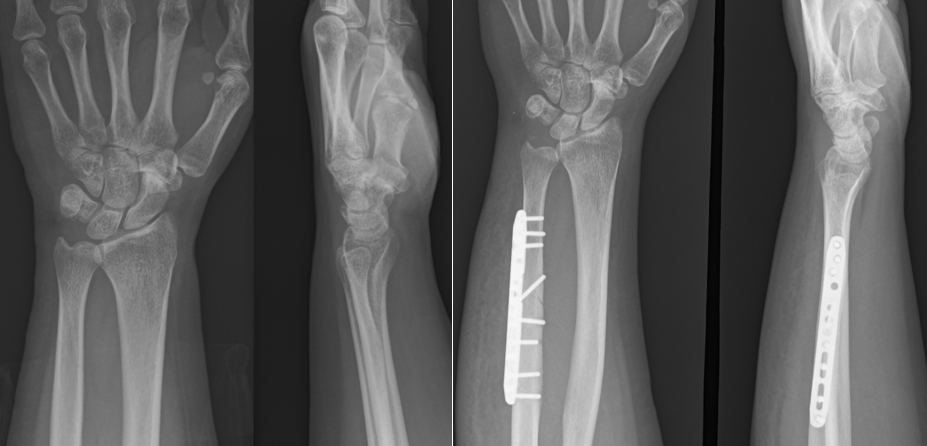

単純X線の他、MRI、手関節造影/CTを行います。単純X線では、TFCC自体は映りません。しかし、骨形態の評価、とくに突き上げ症候群の評価に有用であり、必須の検査の1つです。MRIではTFCCの損傷の有無を評価します。また、ECU腱鞘炎などその他の障害/疾患の有無を確認します。しかしながら、MRIではTFCCの詳細な評価が難しい場合があり、手関節造影/CTが必要となることがあります。手関節造影/CTでは、造影剤を橈骨手根関節内および遠位橈尺関節内に注入しTFCCの円盤部や末梢部、表層部、および小窩(Fovea)部などでの断裂形態を確認します。その他、手根骨間靱帯損傷や手関節尺側部の骨形態について評価します。

手術は関節鏡視下TFCC縫合術(TFCC関節包縫合術、経骨孔TFCC縫合術)、手関節鏡視下デブリドマン、TFCC再建術、尺骨短縮骨切り術、鏡視下尺骨遠位端部分切除(Wafer procedure)などがあります。各術式は年齢、性別、利き手側、スポーツや活動レベル、受傷機転、罹病期間、症状、身体所見などの他、画像評価によるTFCCの状態や突き上げ症候群の有無、DRUJの状態など総合的に評価して決定していきます。手術後は3~6週間、外固定を行います。また、リハビリテーションを行います。状態次第ですが、術後3~6か月程度で日常生活動作やスポーツ復帰が可能となります。

【関節鏡視下TFCC関節包縫合術】

【尺骨短縮骨切り術(術前と術後)】